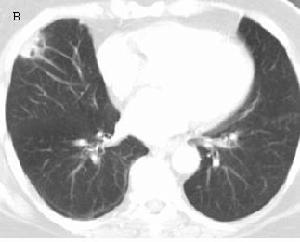

一、B超顯像:這是目前檢查朱古力囊腫比較有效的方法,它的聲像圖呈現出來的影像,如果囊腫周圍的粘連重,邊界就會不清楚,如果囊腫與周圍組織的粘連少,邊界就會很清晰。二、宮頸粘液結晶檢查:雌激素使宮頸粘液稀薄,拉絲度長,並出現羊齒狀結晶,羊齒狀結晶越明顯、越粗,提醒雌激素作用越顯著。若塗片上見成排的橢圓體,提醒在雌激素作用的基礎上,已受孕激素影響。